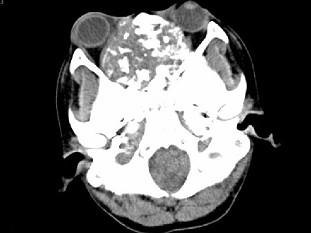

问题 男,26岁,进行性鼻腔阻塞、流涕来院就诊,近两年持续性头痛、头晕.如图所示筛窦区占位灶应诊断为 ( )

选项 A、骨结核伴左上颌窦炎 B、骨纤维异常增殖症伴左上颌窦炎 C、软骨瘤伴左上颌窦炎 D、骨化性纤维瘤伴左上颌窦炎 E、脊索瘤伴左上颌窦炎

答案 C